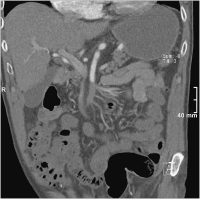

Zweifachstentimplantation

Abbildung 4: Wiedereröffneter Hauptstamm mit Zweifachstentimplantation, Auffüllung der Arkadengefäße, peripher noch embolisch bedingter Verschluss eines Hauptgefäßes

Keywords:

Angiographie

,

Gefäßmedizin

Zweifachstent